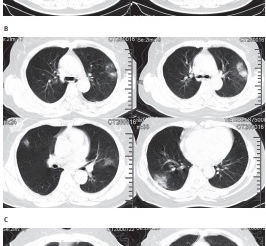

Em dezembro de 2019, um grupo de pacientes com pneumonia de causa desconhecida foi vinculado a um mercado atacadista de frutos do mar em...